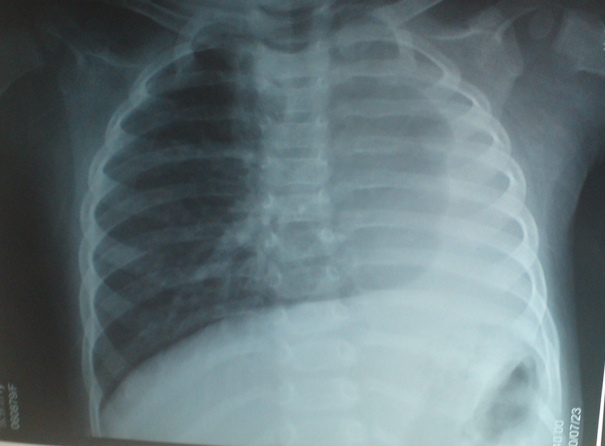

以下是引用liaoqiang在2010-7-26 13:10:00的发言:[br]左侧主支气管未显示,左肺体积明显缩小。右肺体积大。肋间隙不窄。考虑左肺不发育伴右肺代偿性肺气肿、纵隔疝。

以下是引用江广1996在2010-7-26 10:34:00的发言:[br]因为胸廓对称,肋间隙基本正常,故考虑为先天性左肺不发育。[br]如为异物,也会有临床病史。另,这与双胞胎有什么关系,另一个情况怎样?有无检查过?